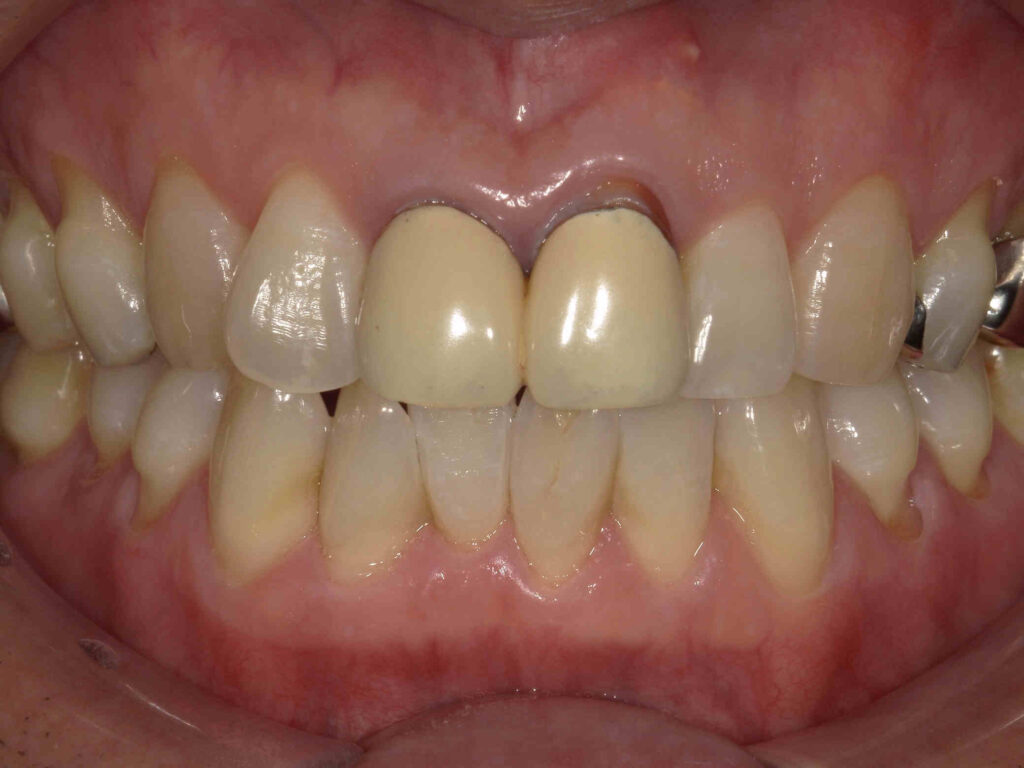

BEFORE

不適合なレジン前装冠が装着されています

| 主訴 | 前歯をキレイにしたい |

|---|---|

| 診断名・ 主な症状 |

前歯部審美障害 |

| 年齢 | 40代男性 |

| 治療内容 | グラデーションジルコニアクラウン |

| 治療期間/ 通院回数 |

1カ月/2回 |

| 費用 | 242,000円 |